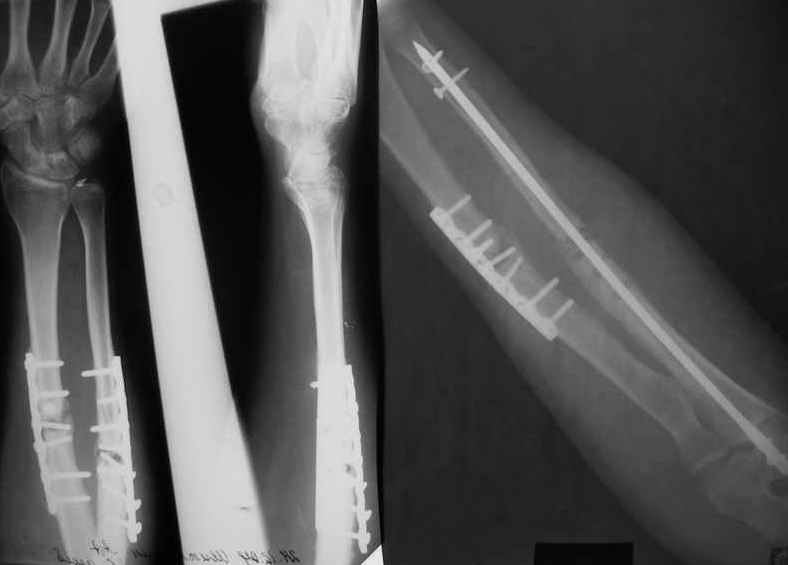

Уважаемые коллеги!Доводим до Вашего сведения наш скромный опыт применения блокирующего остеосинтеза локтевой кости (4случая), четверо пациентов с ложными суставами локтевой кости. Во всех случаях оперировали открыто с костной аутопластикой.Технических проблем введения штифтов не было. В одном случае отвалилась резьбовая часть спицы при прокс. блоке (оставлена как блокирующий винт). Дистальное блокирование осуществляли используя вместо кондуктора сп. Киршнера изгибая ее конец о край кондуктора на необходимую длину до отверстий. Наши первые впечатления классные. Очень быстрая функциональная реабилитация без гипса и консолидация через 2 мц. На представленных фотографиях двое пациентов.Тот, у которого якобы не срастается лучевая кость на АО пластине, уже катался на горн. лыжах, а сейчас опять уехал на Эльбрус -экстремал ,,,нов. С уважением Нагога Александр, ортопедическая клиника ОРТО, Самара.

А зачем же неправильный гвоздь использовать, который нарушает? Наоборот, с помощью гводя нарушенная форма костей очень даже эффективно восстанавливается (см. пример). А неправильный

остеосинтез можно сделать чем угодно.

>Наоборот, с помощью гводя нарушенная форма костей очень даже эффективно восстанавливается (см. пример).

форма восстанавливается, но достаточной стабильности при таком остеосинтезе (пример) достигнуть трудно, ранние движения невозможны, а несращения встречаются как и при любом виде остеосинтеза.